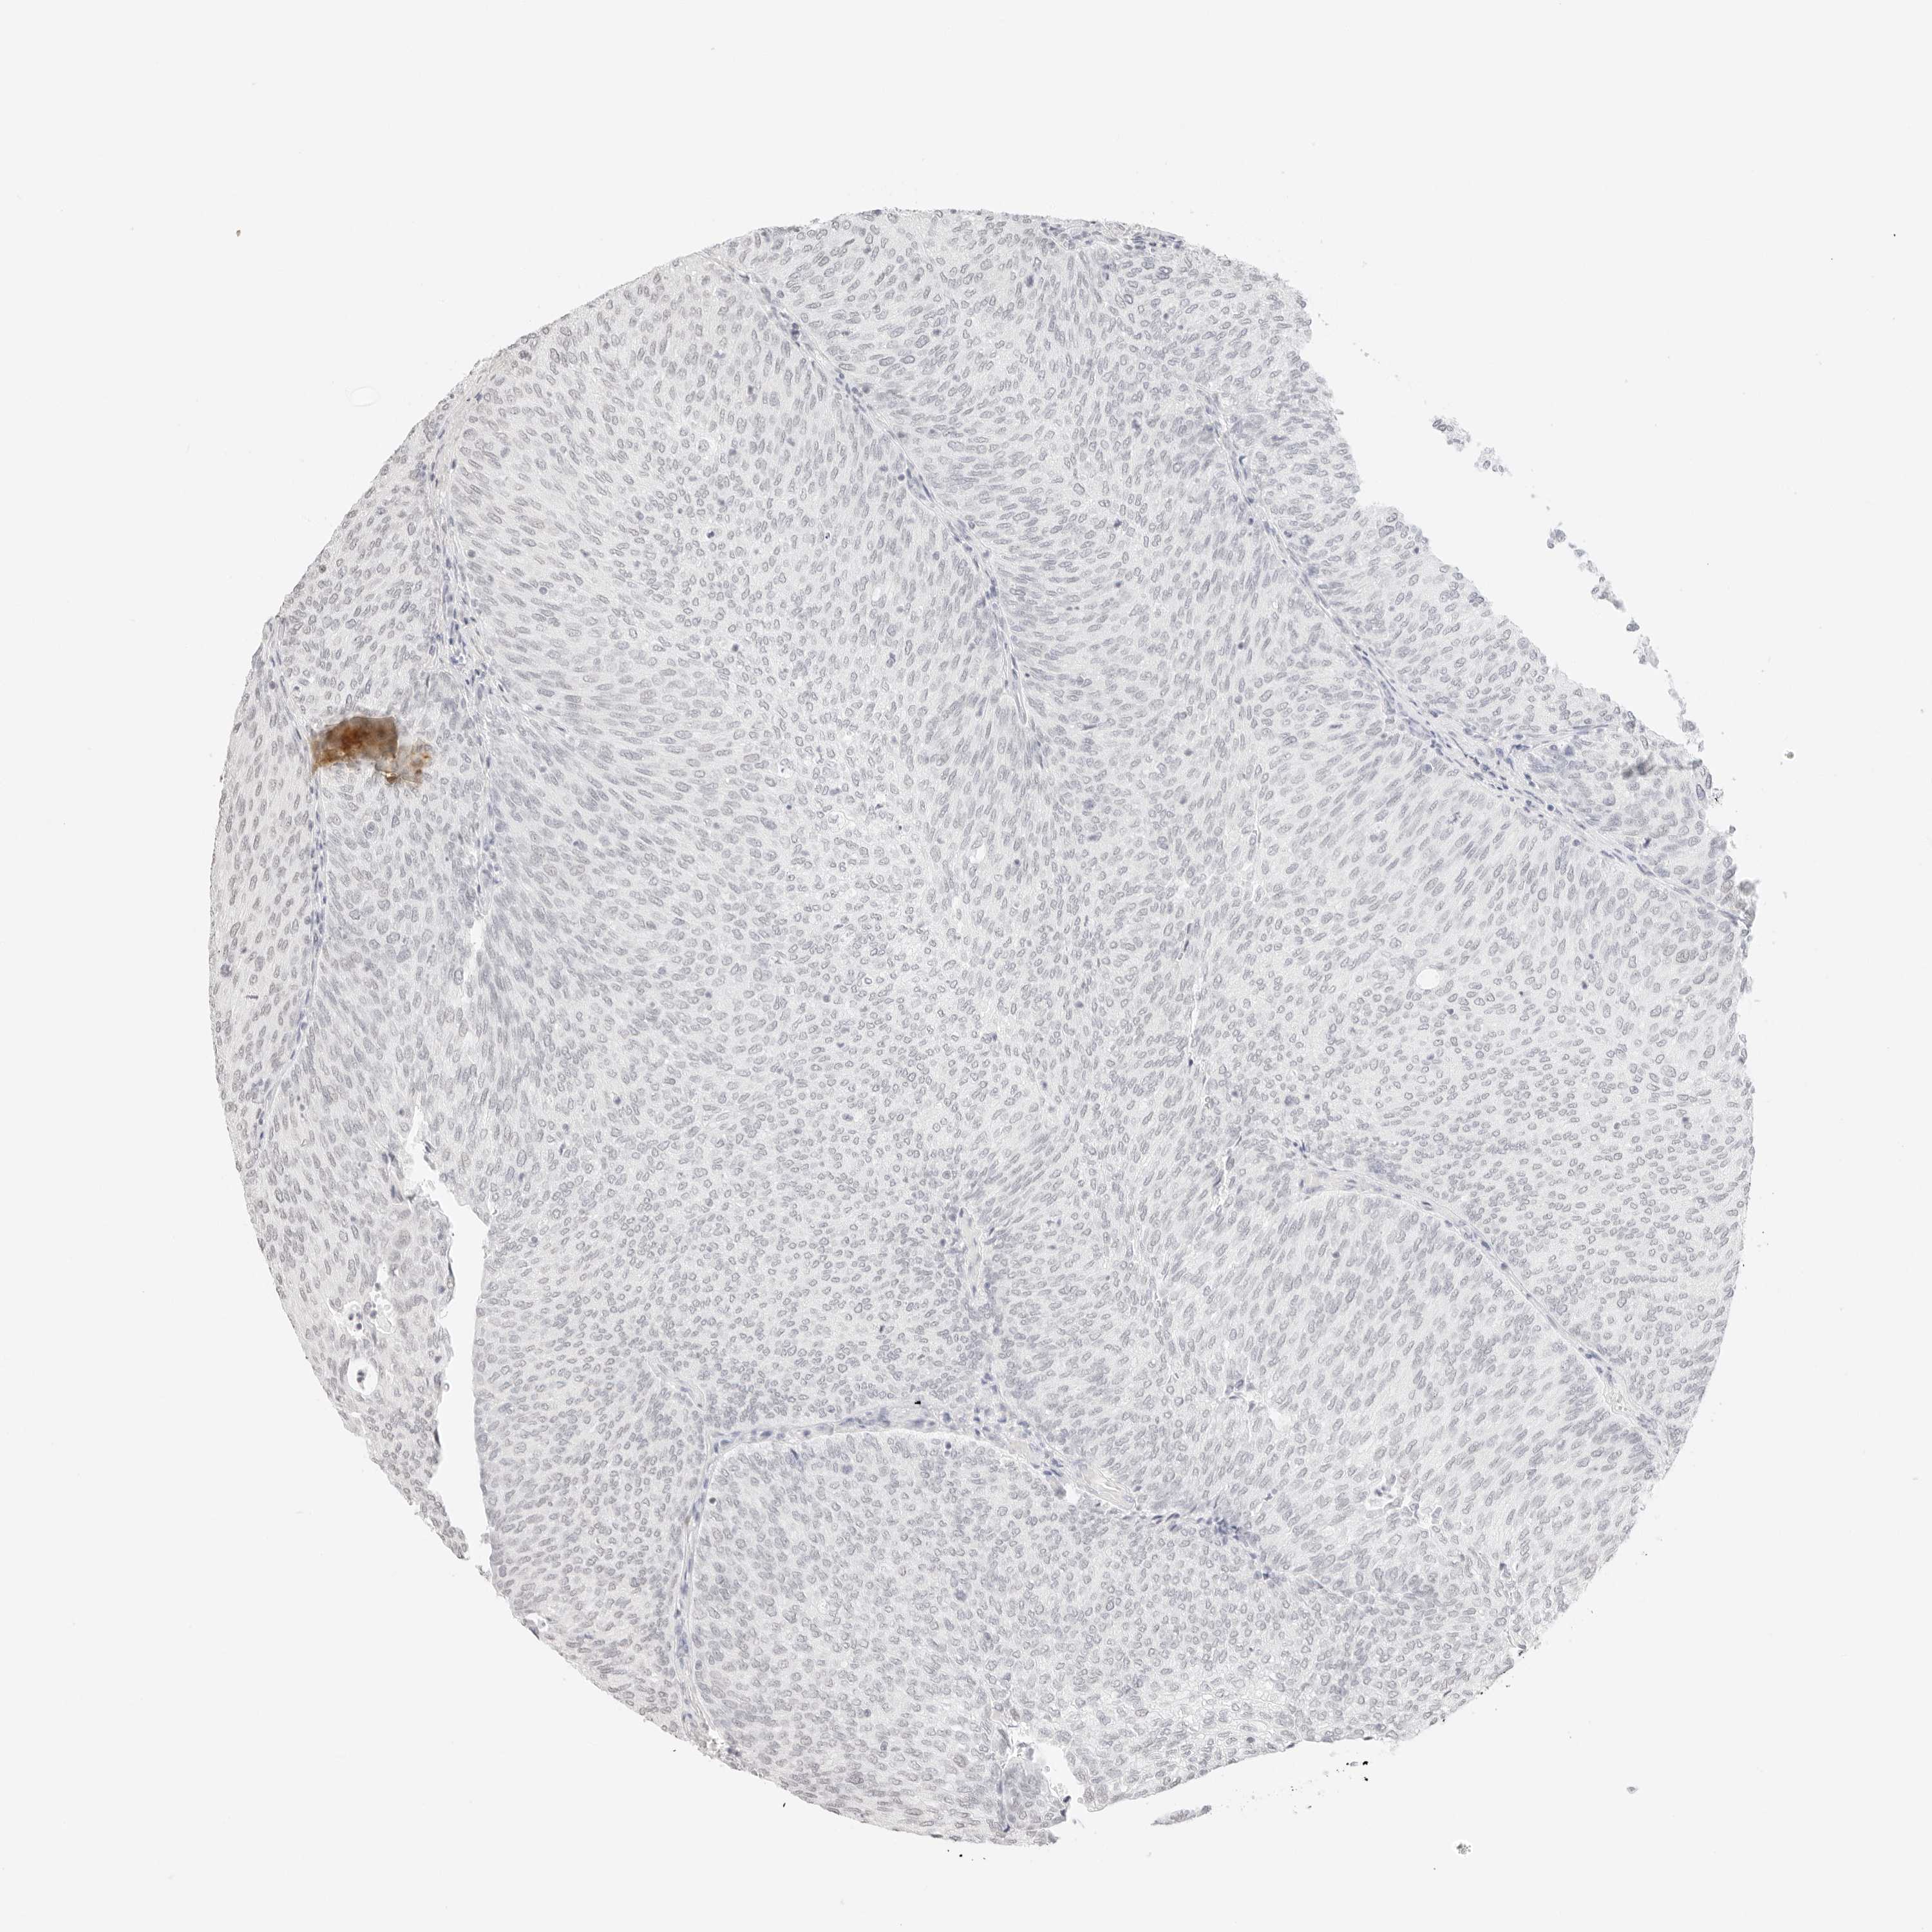

UROTHELIAL CANCER - Protein expressioni

A mouse-over function shows sample information and annotation data. Click on an image to view it in a full screen mode. Samples can be filtered based on level of antibody staining by selecting one or several of the following categories: high, medium, low and not detected. The assay and annotation is described here.

Note that samples used for immunohistochemistry by the Human Protein Atlas do not correspond to samples in the TCGA dataset.

Antibody stainingi

Antibody staining in the annotated cell types in the current human tissue is reported as not detected, low, medium, or high, based on conventional immunohistochemistry profiling in selected tissues. This score is based on the combination of the staining intensity and fraction of stained cells.

Each image is clickable and will lead to virtual microscopy that enables deeper exploration of all samples and also displays staining intensity scores, fraction scores and subcellular localization as well as patient and tissue information for each sample.

Antibody HPA000848

Antibody HPA000868

Antibody CAB025843

Staining

High

Medium

Low

Not detected

Intensity

Strong

Moderate

Weak

Negative

Quantity

>75%

75%-25%

<25%

None

Location

Nuclear

Cytoplasmic/membranous

Cytoplasmic/membranous,nuclear

Urothelial carcinoma, High grade

Urothelial carcinoma, Low grade